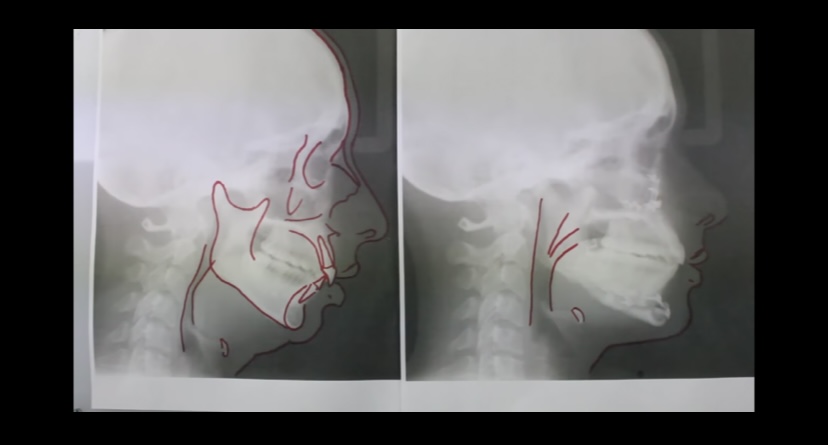

Here they are. Surgeon said he would give me vertical genio in a few months free of charge.

So much fraud in this after picture. The before pic was completely aligned with your side profile but the after photo was taken at a more forward postion which makes the maxilla look more grown. I can prove this because in the before pic you cant see your right eyebrow but in the after pic you can.

^this & looks like youre tilting your head up too which also frauds forward growth.

You def improved though

Looks way better than the original photo where you were bloated, but super tilt frauded lol.

Lol. They want to fraud the forward growth so it looks better than it actually is. Surgeons always fraud after pics

The pirctures are taken very poolry (posture) but overall the results are decent and natural looking. no one is gonna turn into prime photoshopped barret from a bimax. Unfortunately it does not matter (ethnicity tax)